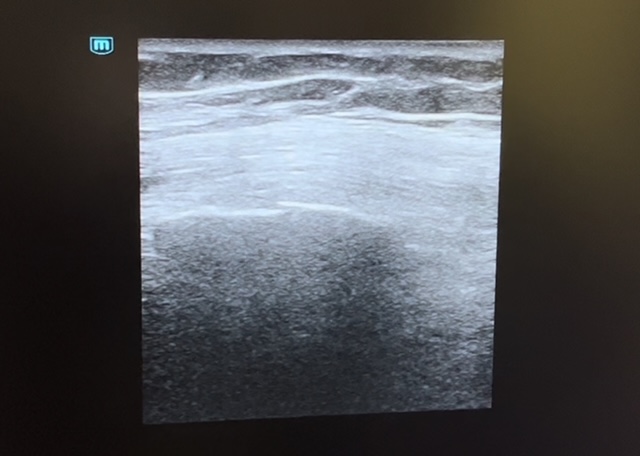

En la exploración física, presenta una saturación basal de 97% sin taquipnea asociada ni uso de musculatura accesoria con una auscultación pulmonar de crepitantes en base izquierda sin otros hallazgos. Ante lo anterior, decidimos solicitar una radiografía de parrilla costal y realizar una ecografía pulmonar en el centro de salud para descartar fractura asociada o neumotórax.

Se evidencia en la ecografía pulmonar sobre el 7º y 8º arco costal izquierdo una posible línea de fractura con falta de contigüidad en los rebordes costales sin evidenciar signos de neumotórax.

Posteriormente, se solicitó una radiografía de parrilla costal de carácter urgente que confirmó dichos hallazgos.

Por lo tanto, se trata de un caso de una fractura costal de 7-8º arco costal izquierdo tras caída casual.